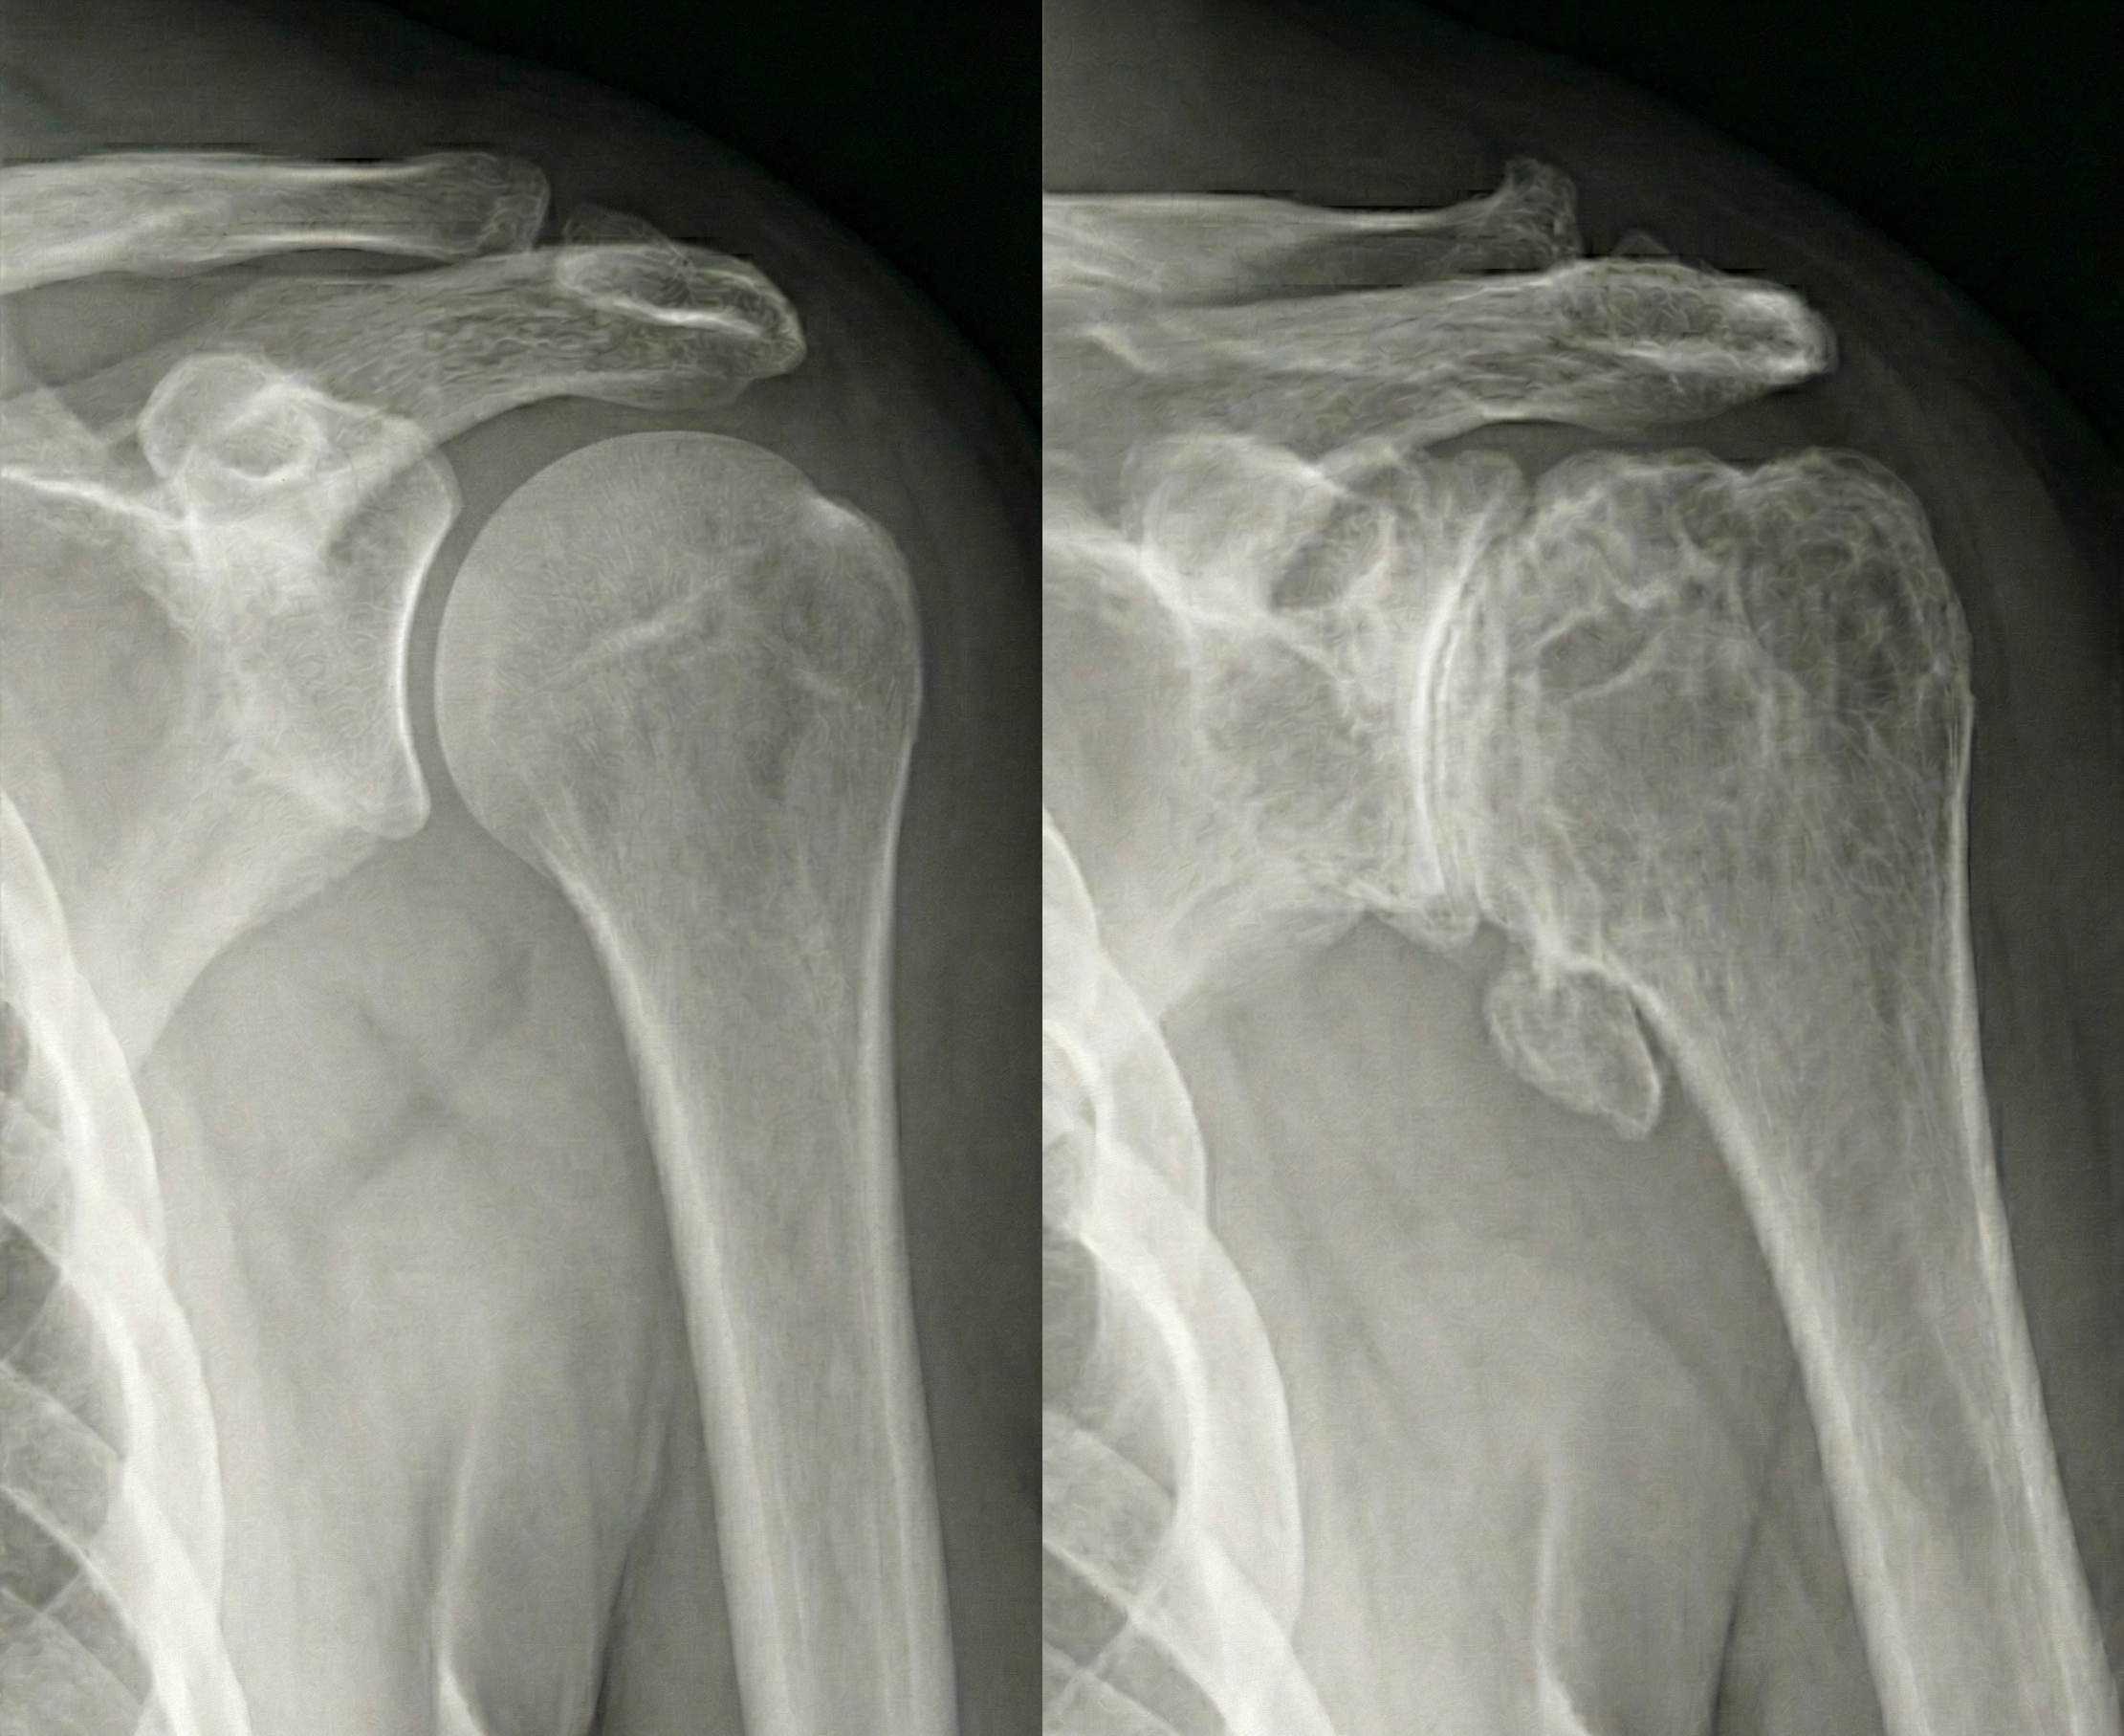

Comparison of healthy and arthritic shoulder xrays (radiographs), showing a healthy shoulder with healthy cartilage and an arthritic shoulder with eroded cartilage and bone spurs (osteophytes).  - Dr. Kevin Wall, Richmond, VA

As the cartilage thins, eventually, the underlying bone is exposed, leading to a "bone-on-bone" grinding sensation. The nerve endings that live in this exposed bone are a common cause for increased pain as arthritis progresses. The body responds to this cartilage loss by creating bone spurs (osteophytes) around the joint, and the surrounding tissues can get inflammed and tight. Unlike the hip or knee, shoulder arthritis can be fairly well tolerated until it reaches a critical tipping point of stiffness and pain. An important note about arthritis anywhere in the body: science does not yet have a way of regenerating lost cartilage - once arthritis begins, the cartilage loss will only continue to worsen. Symptoms may wax and wane but on a cellular level, the cartilage will never regrow.

Shoulder arthritis is most commonly diagnosed on x-ray, however additional imaging is often required (such as CT and MRI) to better characterize what is happening to the bone and soft tissue around the shoulder joint.